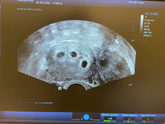

12 марта 2022 13:53

Заметила изменения в работе ЖКТ, почти целый день чувствую голод вперемешку с сильной тошнотой, ем немного, но очень часто, чтобы как-то облегчить. В целом лишний вес не грозит, я очень тощая (51кг/164см). До беременности я столько физически в себя не … Читать далее